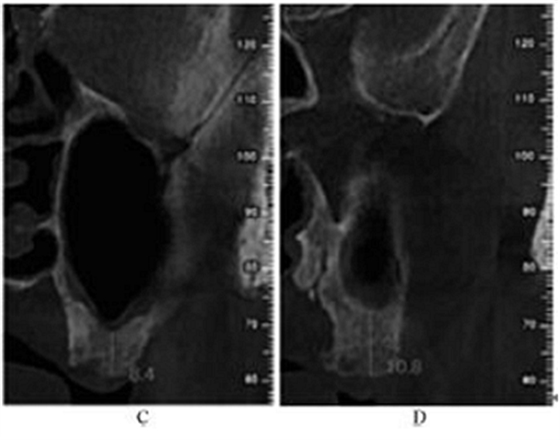

术后5个月,患者无流涕、鼻塞,无其他自觉症状。CBCT示:左侧鼻甲基本恢复正常,上颌窦高密度影较前明显减少,仍有少量黏膜增厚。26牙RBH8.1mm,27牙RBH8.4mm(图4)。拟26~28牙种植修复。

图4 种植前CBCT。注:A,矢状面;B,26颊舌向切面;C,27颊舌向切面;D,28颊舌向切面。